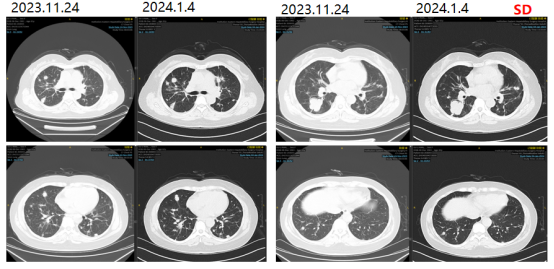

更换治疗方案为西妥昔单抗+XELIRI方案。2023-12-05、2024-01-03分别予西妥昔单抗+XELIRI方案 q3w。

图7影像学复查结果

2024-01-26、2024-02-20、2024-03-16继续予靶向+XELIRI方案化疗4疗程。

出现粒细胞缺乏,化疗后48小时皮下注射PEG-rh-GCSF。

2024-04-09评估疗效疾病稳定(SD)。